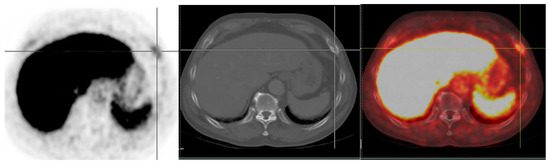

Figure 4.

An example of nonspecific bone uptake. 18F-PSMA PET/CT scan performed on a 71-year-old male with a history of 3 + 3 Gleason score PCa treated with radical prostatectomy (initial PSA levels of 6.3 ng/mL) for initial staging. PET/CT scan revealed a focal PSMA uptake at lateral aspect of right 6th rib (SUVmax of 5.08) without associated osteolytic/blastic lesion. Pathological report from CT guided-biopsy at this lesion revealed benign bone lesion. Follow-up serum PSA in this patient was still low (nadir 0.006 ng/mL).